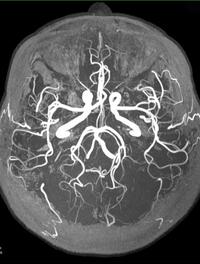

Après une thrombose artérielle responsable d’une ischémie cérébrale, les thrombolytiques augmentent la conversion du plasminogène en [...]